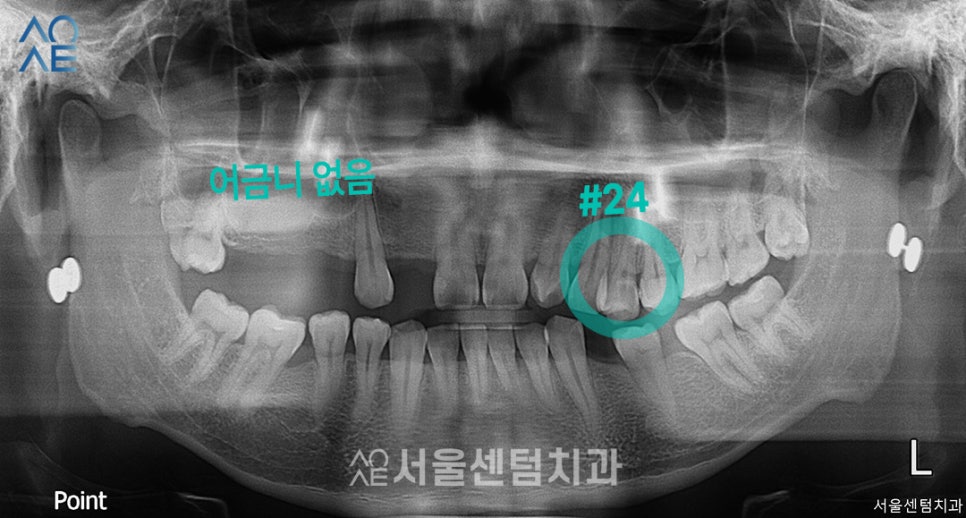

상담에서 가장 먼저 저에게 하신 말씀은

아마 임플란트랑 치료할게 많을 것 같다는

걱정이었습니다.

어금니는 이미 상실한 상태였고

다른 치과에서도

임플란트가 필요하다는 말을 들으셨다고 합니다.

약간의 겁을 먹으신 것 같아서

잘 달래드리며 구강검진 및 상담을 진행했습니다.

| 🦷현재 상태 &치료 계획🦷 |

|---|

| (1) 현재 상태🔹기존 보철물 치료를 하셨음→보철물 제거 후 엑스레이 촬영 필요🔹잇몸뼈 부족 |

| (2) 치료 계획🔹24번 치아 발치🔹위/아래 총 7개 임플란트 식립+뼈이식 필요 |